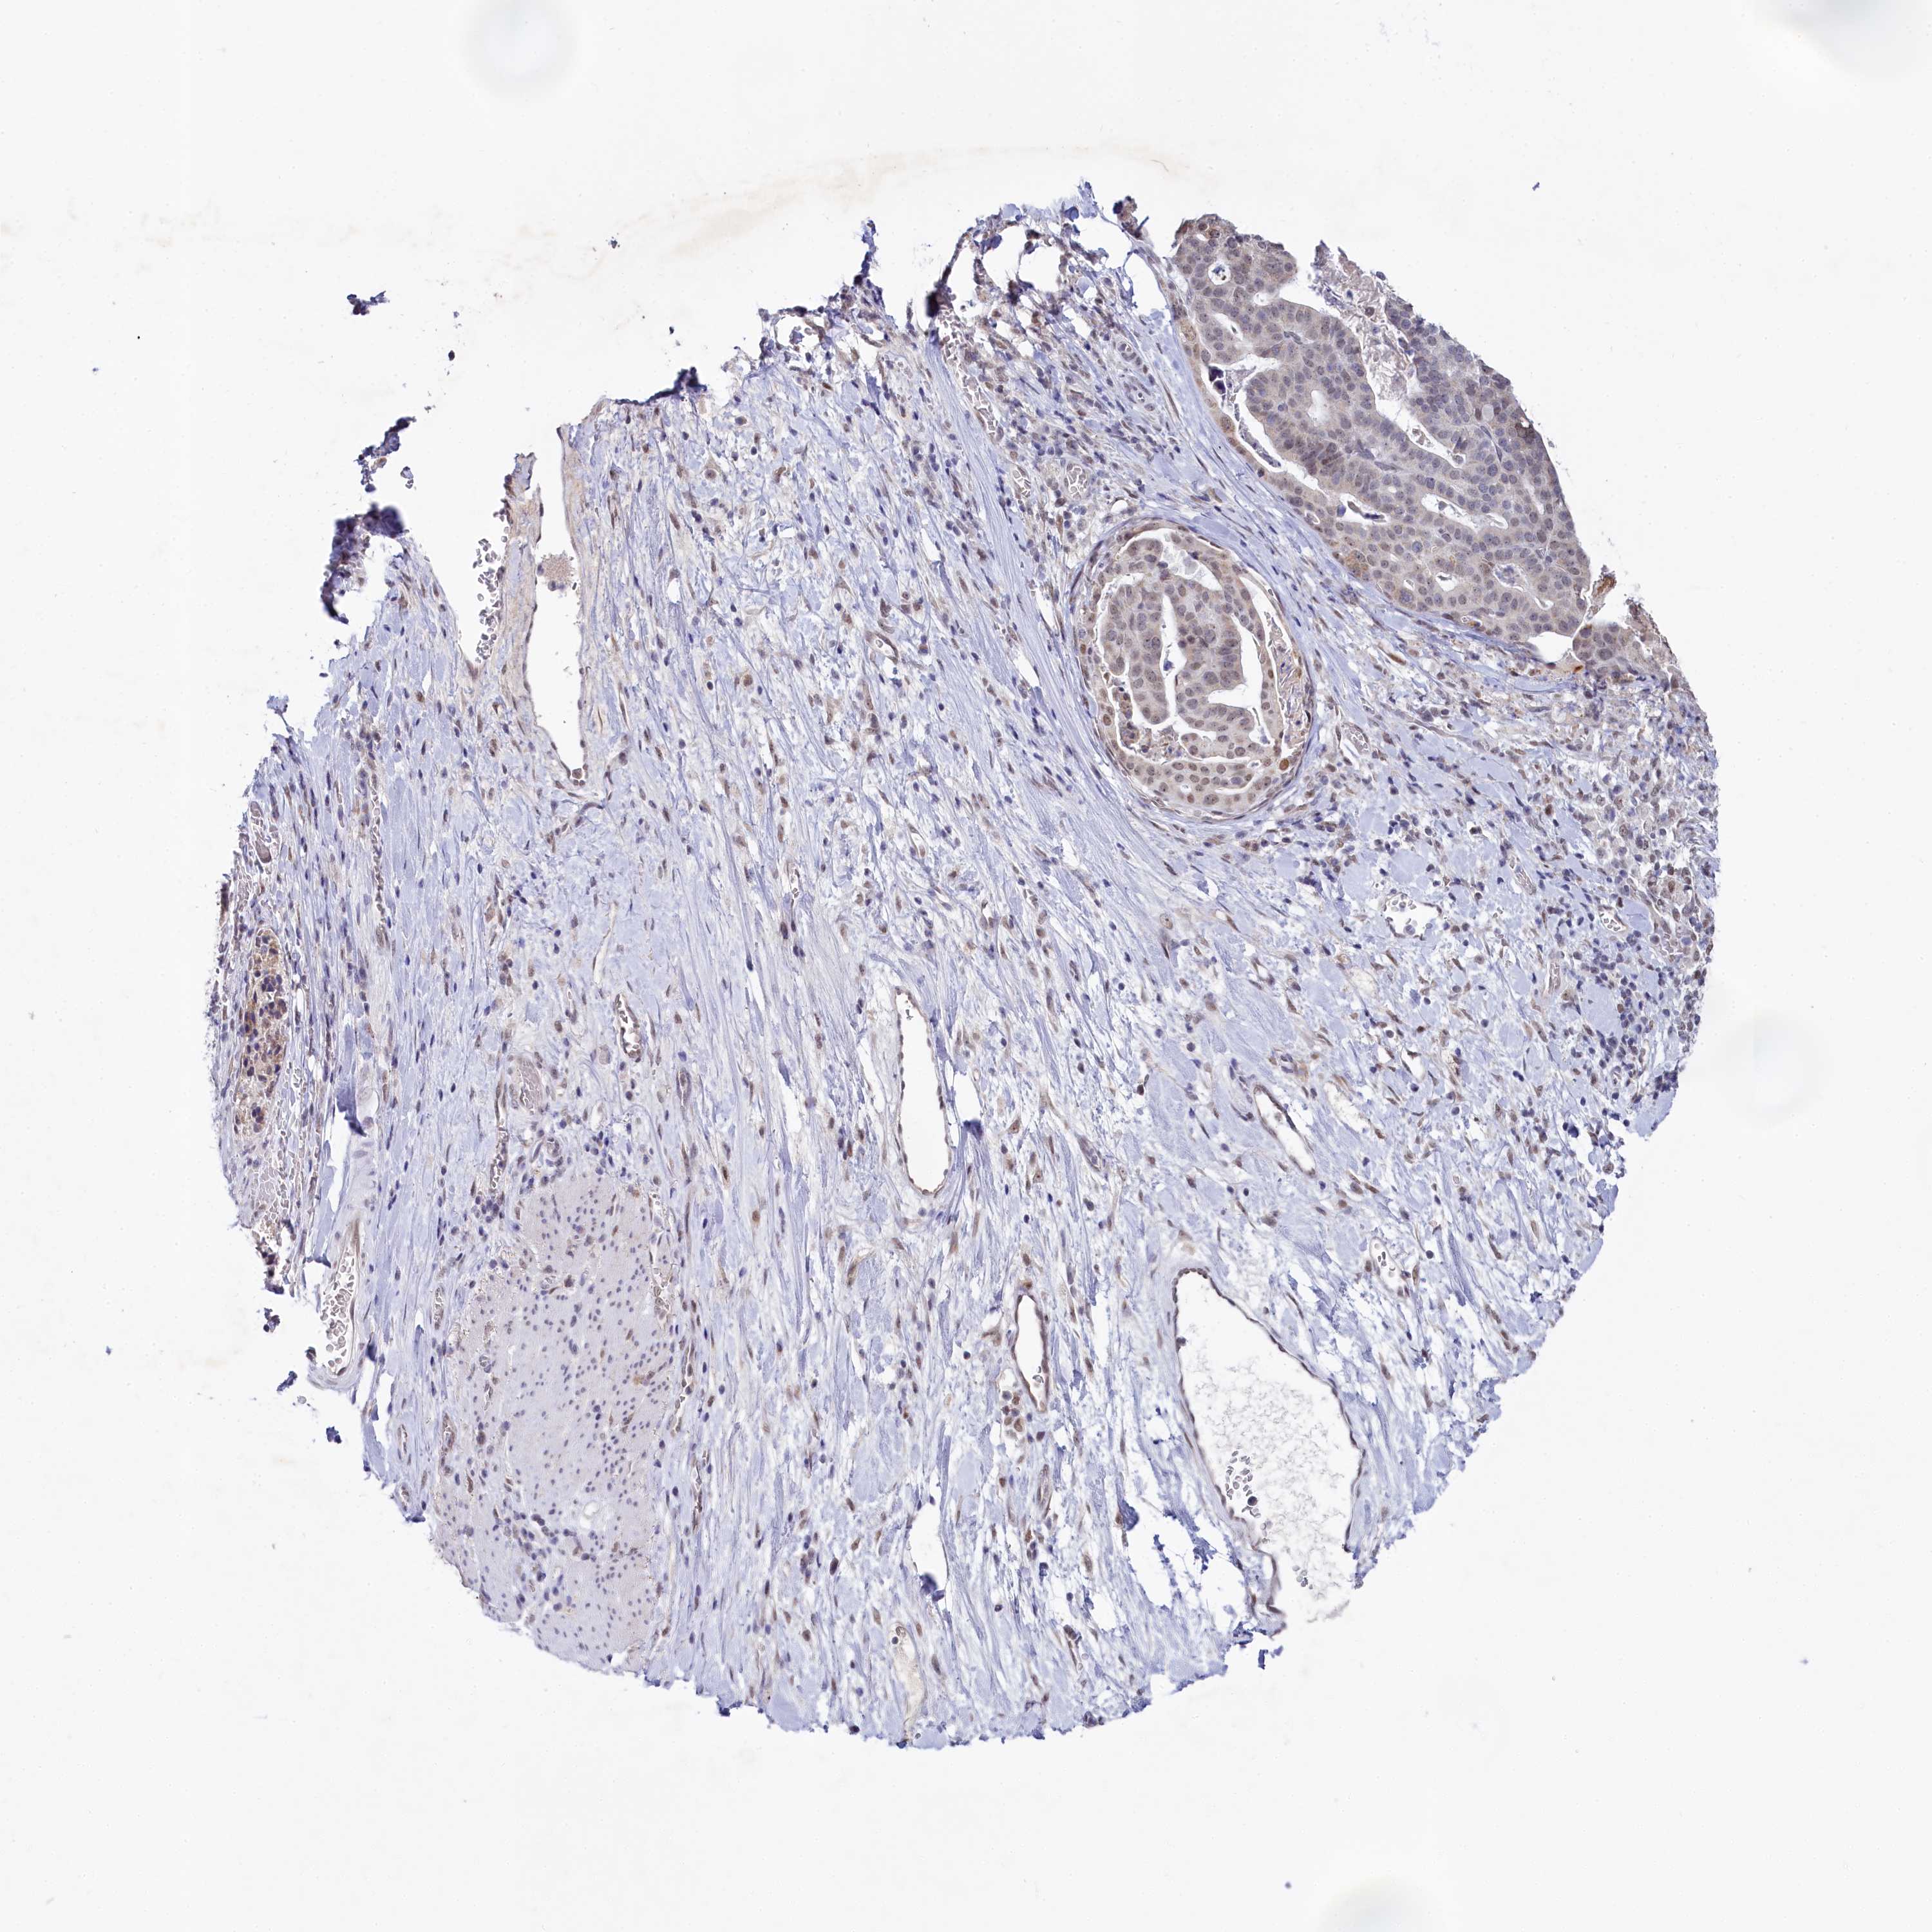

STOMACH CANCER - Protein expressioni

A mouse-over function shows sample information and annotation data. Click on an image to view it in a full screen mode. Samples can be filtered based on level of antibody staining by selecting one or several of the following categories: high, medium, low and not detected. The assay and annotation is described here.

Antibody stainingi

Antibody staining in the annotated cell types in the current human tissue is reported as not detected, low, medium, or high, based on conventional immunohistochemistry profiling in selected tissues. This score is based on the combination of the staining intensity and fraction of stained cells.

Each image is clickable and will lead to virtual microscopy that enables deeper exploration of all samples and also displays staining intensity scores, fraction scores and subcellular localization as well as patient and tissue information for each sample.

Antibody HPA038902

Antibody HPA038903

Staining

High

Medium

Low

Not detected

Intensity

Strong

Moderate

Weak

Negative

Quantity

>75%

75%-25%

<25%

None

Location

Nuclear

Cytoplasmic/membranous

Cytoplasmic/membranous,nuclear

Adenocarcinoma, NOS

Adenocarcinoma, High grade